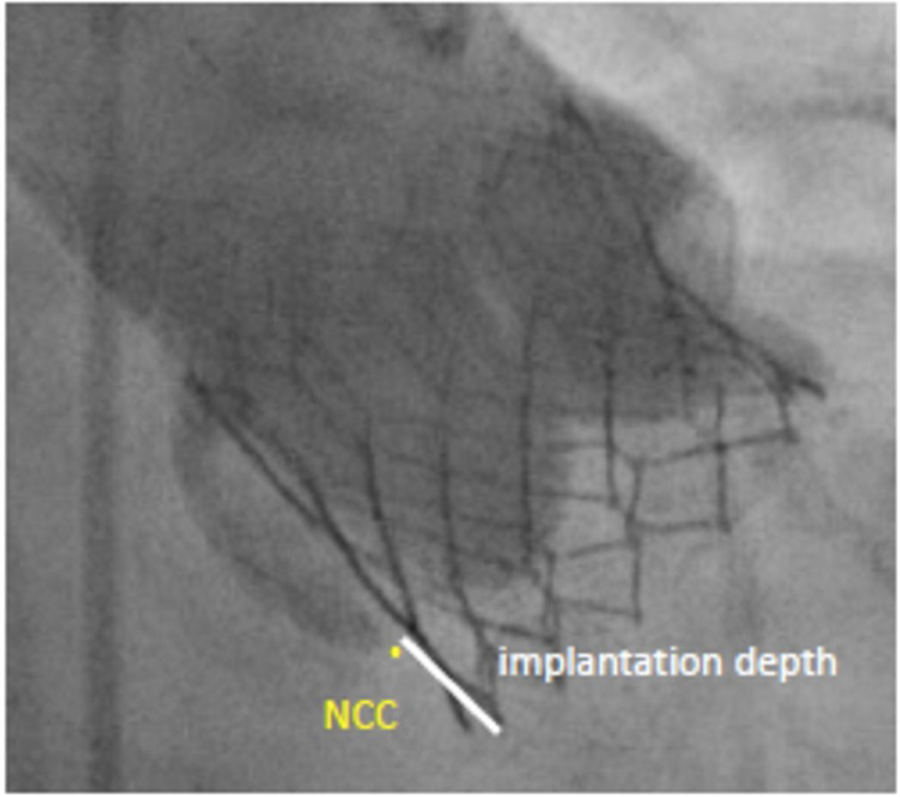

PPI was considered in patients with persistent complete high grade atrioventricular block after TAVR. Assessment of the prothesis implantation was based on post-procedural evaluation of aortography and was carried out using a dedicated software (CAAS 7.4., Pie Medical Imaging, Maastricht, the Netherlands). ID was expressed as the maximal distance of the native aortic annulus plane on the side of the non-coronary cusp (NCC) to the most proximal edge of the implanted valve in the left ventricle (Figure 3). ID was measured in COP as well as TCC projection in all patients, with the greater distance used as the true ID.

Figure 3

Implantation depth. Measurement from the non-coronary cusp (NCC) to the distal end of the intraventricular portion of the implanted valve.